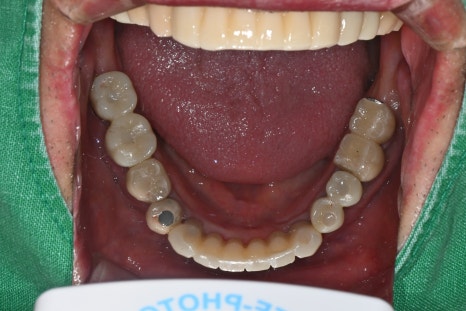

Right photo: The lower teeth had a missing crown and a broken implant, so overall reconstruction was needed.

Right photo: The final prosthesis was accurately secured to the implant placed in the extracted site.

Left photo: Front view of the completed prosthesis. Both esthetics and function were restored satisfactorily.